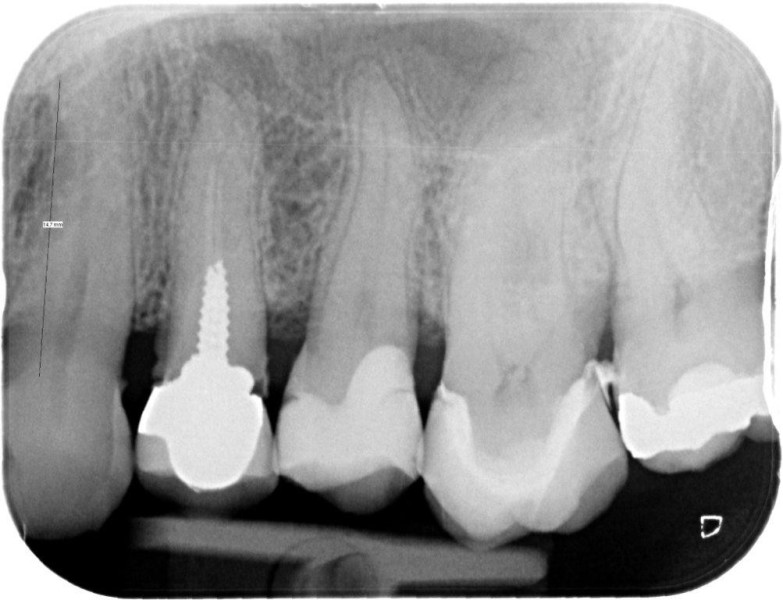

Premolar retreatment